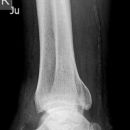

Maisonneuve

Spiralfraktur Tibia